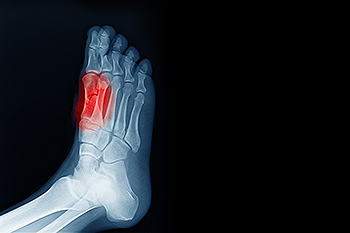

Foot pain can develop from a range of conditions that affect the bones, soft tissues, skin, or nerves. One frequent source of foot pain is plantar fasciitis. This is a repetitive stress condition resulting from inflammation of the thick band of tissue that runs along the bottom of the foot. Bunions are another cause, creating a visible bump near the big toe joint that can become painful and swollen. Tendon injuries, such as Achilles tendonitis, cause pain and stiffness near the heel, especially after activity. Nerve compression in the foot, such as tarsal tunnel syndrome, produces tingling, burning, or shooting sensations. Stress fractures, often related to repetitive impact or overuse, lead to localized pain and swelling that worsens with movement. A podiatrist can evaluate the structure of your foot, using imaging to confirm the cause of the pain. If you are experiencing any type of foot pain, it is suggested that you make an appointment with a podiatrist for a diagnosis and treatment options.

To figure out the cause of foot pain, podiatrists utilize several different methods. This can range from simple visual inspections and sensation tests to X-rays and MRI scans. Prior medical history, family medical history, and any recent physical traumatic events will all be taken into consideration for a proper diagnosis.